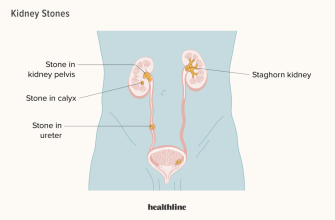

Kidney stones are a common condition that affects millions

Kidney stones are a common and painful condition that